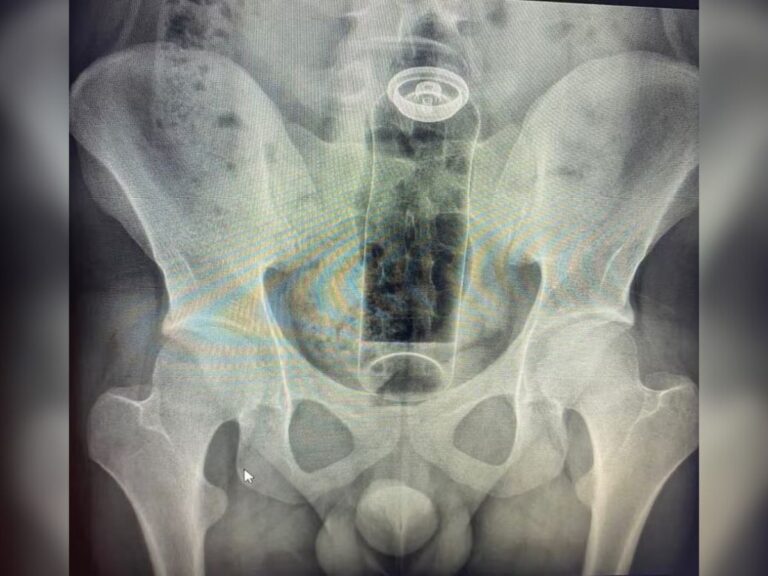

Paciente com desodorante no reto

Paciente com desodorante no reto (Arquivo pessoal / G1)

Um jovem de 19 anos precisou ser internado às pressas após um frasco de desodorante ficar preso em seu reto, em um caso que mobilizou uma equipe médica para evitar complicações graves. O rapaz procurou atendimento hospitalar depois de perceber que o objeto havia migrado para o interior do intestino, tornando impossível qualquer tentativa de remoção manual.